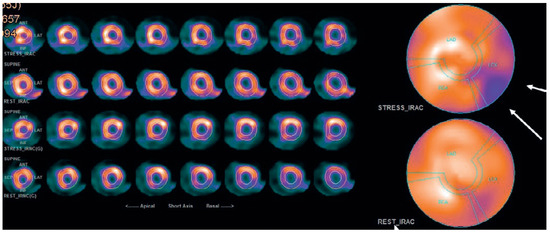

Myocardial infarction with nonobstructive coronary arteries (MINOCA): Myocardial infarction (MI) with non-obstructive coronary arteries (MINOCA) is defined as MI according to the fourth universal definition of MI [1] without coronary stenosis ≥50% on...